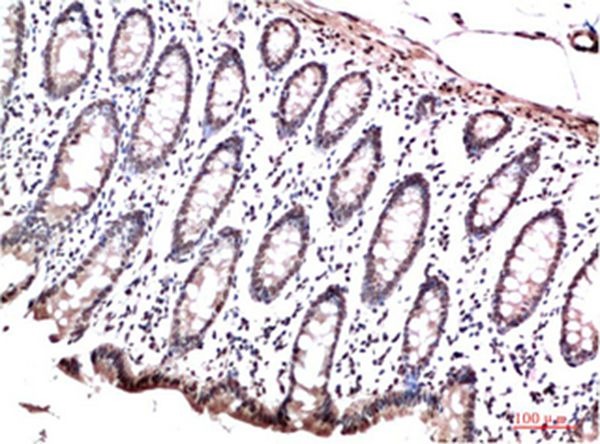

| Verified Activity | 1. Western blot analysis of 1) Hela Cell Lysate, 2)3T3 Cell Lysate, 3) PC12 Cell Lysate using HP-1γ Mouse mAb diluted at 1:1000. 2. Immunohistochemical analysis of paraffin-embedded Human Colon Carcinoma Tissue using HP-1γ Mouse mAb diluted at 1:200. 3. Immunohistochemical analysis of paraffin-embedded Human Placenta Tissue using HP-1γ Mouse mAb diluted at 1:200. 4. Immunohistochemical analysis of paraffin-embedded Human Colon Carcinoma Tissue using HP-1γ Mouse mAb diluted at 1:200. ![]() ![]() ![]() ![]() |